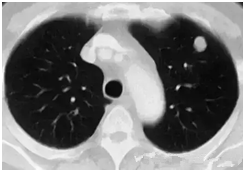

肺部小結(jié)節(jié)通常是指影像檢查(X線或者CT)中發(fā)現(xiàn)的直徑≤2cm的類圓形病灶,≤3cm的稱為結(jié)節(jié),>3cm的稱為腫塊。

也有學(xué)者認(rèn)為,分得太細(xì)并無(wú)意義,例如2.2cm的結(jié)節(jié)與1.9cm的小結(jié)節(jié),臨床上并沒(méi)有本質(zhì)的區(qū)別。在這里我們統(tǒng)一把≤3cm的結(jié)節(jié)統(tǒng)稱為肺部小結(jié)節(jié),在肺部小結(jié)節(jié)中,60%—70%為良性結(jié)節(jié),30%—40%的結(jié)節(jié)方為惡性結(jié)節(jié),所以,發(fā)現(xiàn)肺部小結(jié)節(jié)切勿驚慌。

結(jié)節(jié)的大、小與良、惡性有一定的相關(guān)性,當(dāng)肺部結(jié)節(jié)>3cm的病灶多為惡性,而微小的結(jié)節(jié),良性的可能性居多。

我們常看到的影像學(xué)描述中的“磨玻璃結(jié)節(jié)(GGO)”,其中一部分是非典型腺瘤樣增生(AAH)或原位腺癌(AIS),結(jié)節(jié)內(nèi)部的實(shí)變與生長(zhǎng)速度的加快(范圍變大)常意味病變性質(zhì)的轉(zhuǎn)變,可以逐步演變?yōu)槲⒔?rùn)腺癌(MIS)、浸潤(rùn)性腺癌(IAC)。